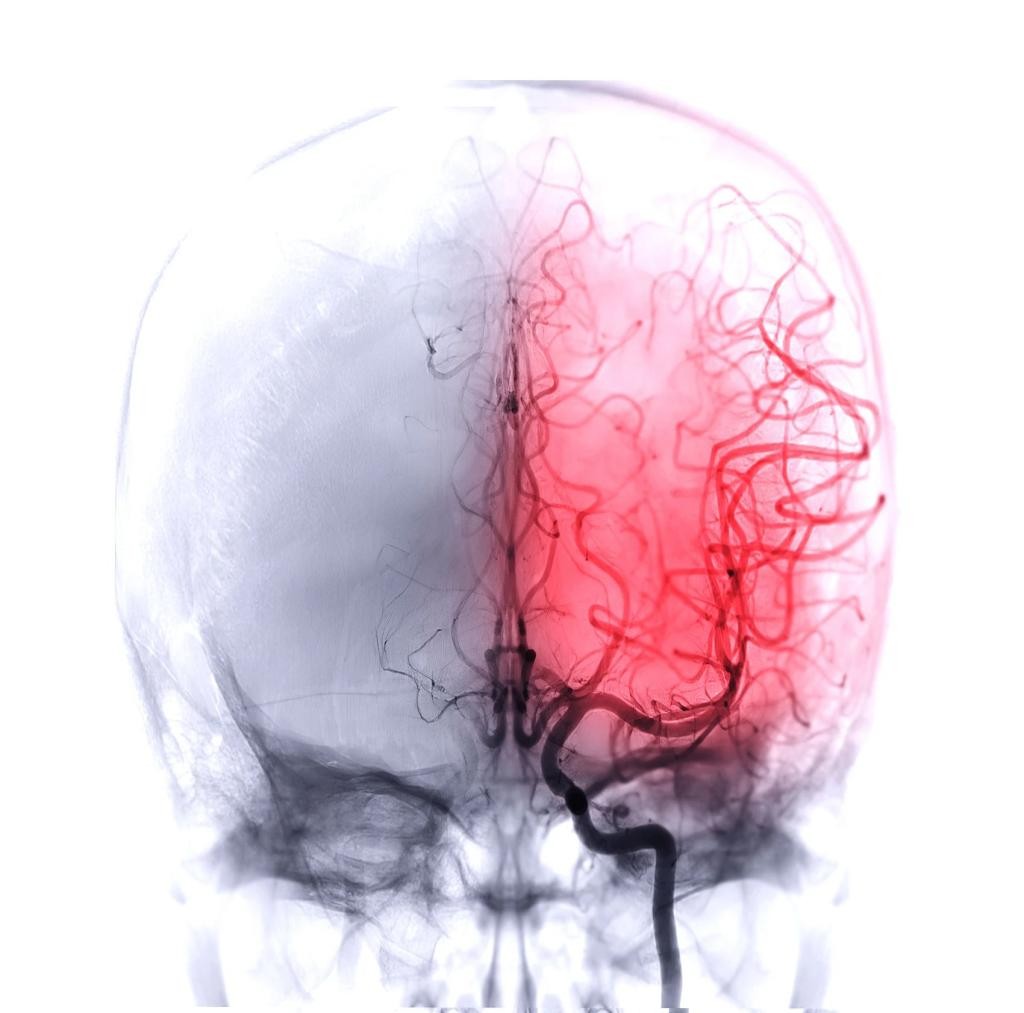

指导专家中南大学湘雅医院放射科 周高峰 副主任技师脑血管疾病是人类健康的杀手之一,有着“三高一多”的特点——发病率高、致残性高、死亡率高,且并发性多——尤其是对中老年人而言,更像一个偷偷埋伏却突然发出致命一击的“隐形杀手”。虽然这个“杀手”有“隐形”的能力,但医生们也有一双智慧的“透视眼”来帮忙。一什么是CT血管成像CTA也称CT血管造影术,是一种非创伤性血管成像技术,通过外周静脉或者中心静脉注射含碘造...